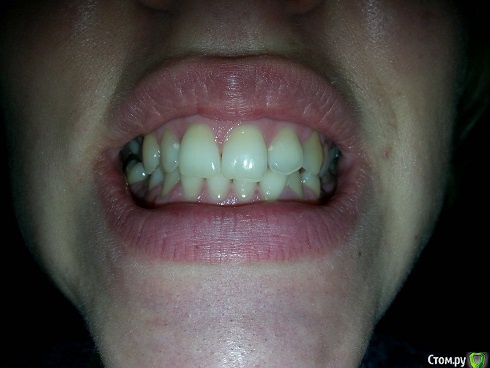

zimazima Опубликовано 20 ноября, 2015 Поделиться Опубликовано 20 ноября, 2015 Добрый вечер!Опытные ортодонты, скажите, пожалуйста, будет ли необходимо в моем случае удалять нижние 4ки? Какова вероятность того что НЧ выйдет вперед после ношения брекетов? предыстория: в 17 лет носила брекеты на ВЧ, т.к. слева клык рос поверх ряда удалили 4ку и поставили на ее место клык...при этом ВЧ потеряла симметрию((и кажется что проявилось это спустя годы (сейчас мне 30). и теперь за счет того что НЧ не ровнялась зубы начали разворачиваться опять... вопросы:- какова вероятность того что удаление нижних 4к не потребуется при лечении?(ортодонт говорит что можно поносить пол года и посмотреть в процессе, имеет ли это смысл? или лучше не терять время, может все очевидно?...)- можно ли оставлять 8ки?- реально ли вернуть центр ВЧ на место если удалить 4ку слева?- при удалении нижних и верхних 4к как сильно сузится лицо и подбородок станет ли еще более выпирающим? (лицо у меня и без того узкое и длинное, достаточно большой нос картошкой и выступающий подбородок) не станет ли хуже?- не будет ли после лечения других проблем с искривлением лица (оно у меня сейчас не симметричное - глаза на разном уровне))), на фото вижу особенно это(( в общем в жизни не так вроде бы все и плохо выглядит - на фото просто кошмар - сама посмотрела и уже готова на все.волнуюсь не будет ли хуже в моем случае? очень благодарна за любые ответы - советы - комментарии! спасибо!выложу доп фото по запросу любые нужныеЗлобина А.В. Заключение.pdf Ссылка на комментарий